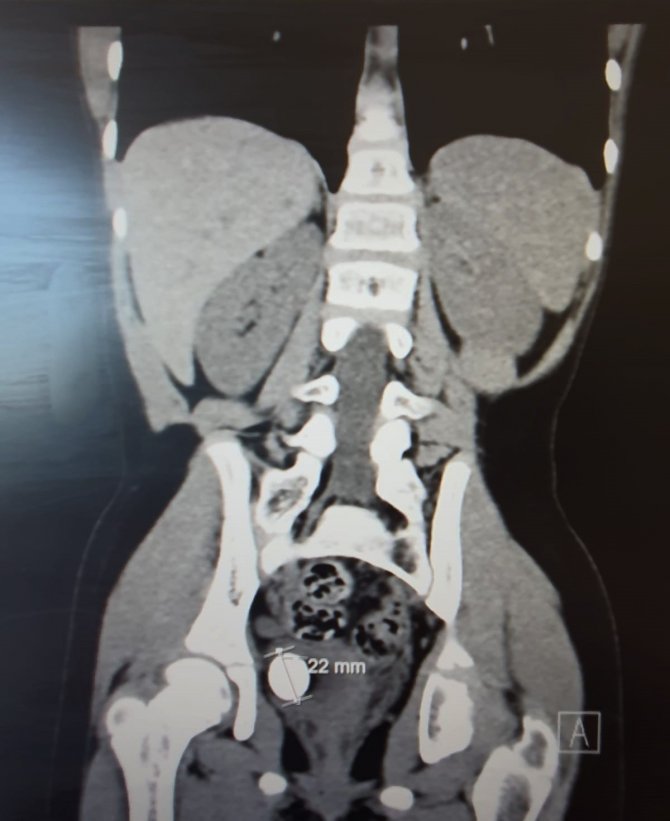

Düzce Üniversitesi Hastanesi Üroloji Kliniği'ne sık idrar yolu enfeksiyonu, kanlı idrar ve iştahsızlık şikayet ile başvuran 8 yaşındaki Dilanur A.'nın mesanesinde 22 mm'lik taş saptandı. Dış merkezlerde açık ameliyat önerilen hastaya yapılan tetkiklerde taşın endoskopik lazer tedavi edileceği belirlenerek ameliyat kararı alındı.

Ameliyat öncesi hazırlıkların tamamlanmasıyla anabilim dalından Dr. Alpaslan Yüksel tarafından operasyona alınan hastanın 22 mm'lik taşı, endoskopik lazer tedavisiyle kırıldı. Operasyon sonrası sağlığına kavuşan hasta, işlemin ardından ertesi gün taburcu edildi. 10 gün sonra kontrole gelen hasta, tüm şikayetlerinin kaybolduğunu ve iştahının açıldığını belirtti.